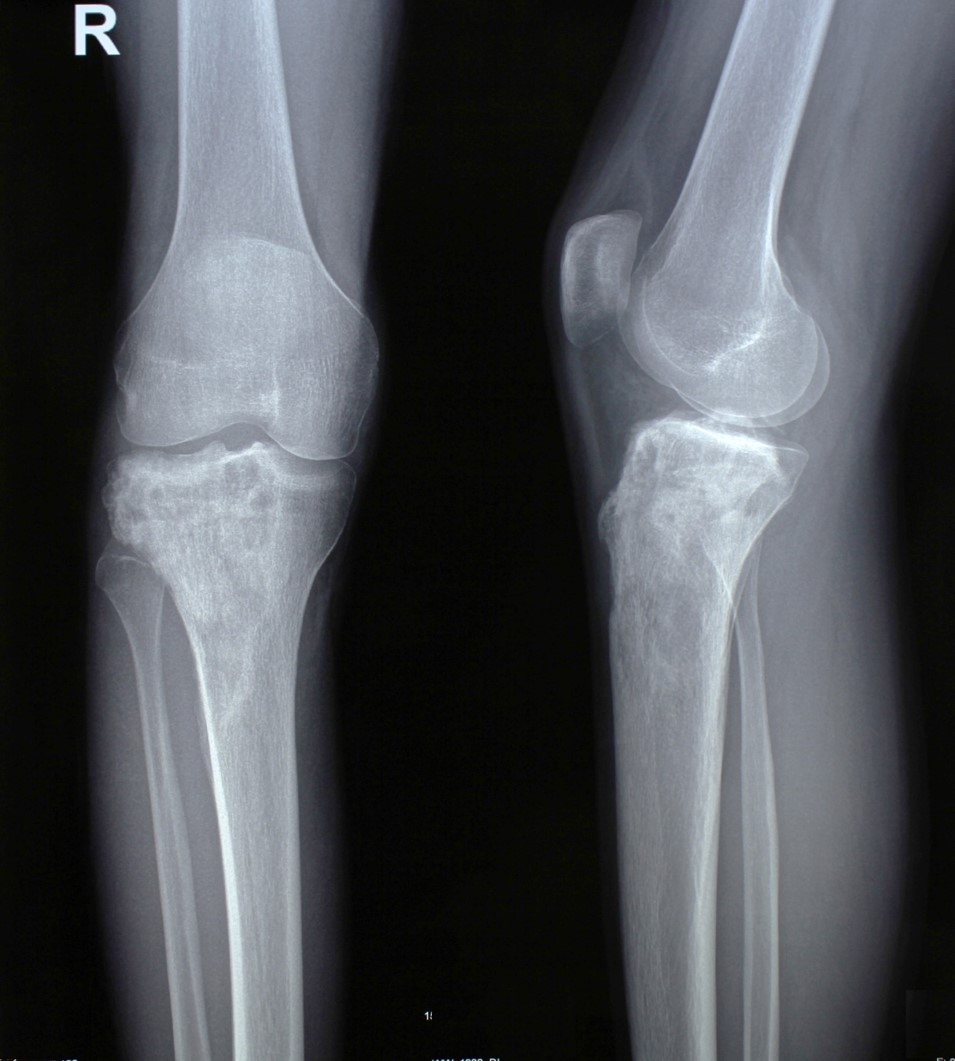

2. Остеосаркома большеберцовой кости

17-летний юноша обратился в МЦ ''Наири'' с жалобами на боли в области коленного сустава. После прохождения обследования у пациента была диагностирована остеосаркома большеберцовой кости.

До операции